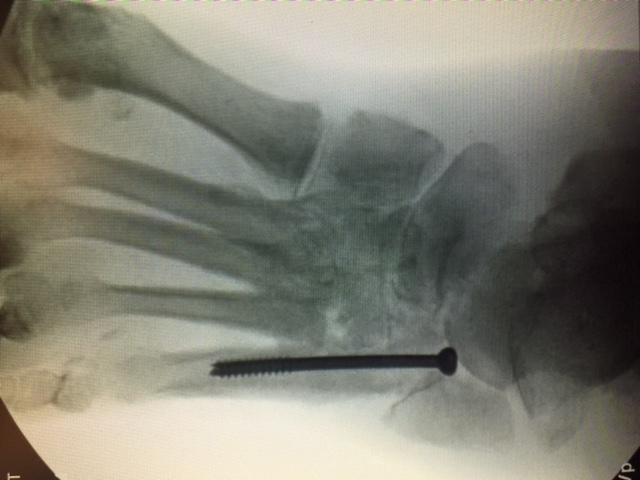

Unpublished research from our institution also suggests that placing a screw across the subtalar joint produces better long-term survivability. This makes sense to our team from the perspective of bending moments across the arch of the foot. The more beams one adds to a static medial column system, the more beams share the load. Therefore, placing a beam through the second metatarsal, into the lesser tarsus and into the talar neck shares the load of the medial column of the foot.

Additional emerging concepts with regard to beaming within our institution include the use of titanium trusses for cases involving significant midfoot bone loss. We have performed several of these reconstructions with good long-term limb salvage results. Structurally speaking, titanium trusses accept and resist the same loads as beams. A benefit of a truss is the bending stiffness and bending strength is a factor of 4 or above the structural mass required for the midfoot, which can easily resist failure.

In our experience, the mechanical forces of the midfoot in compression are enough to place the wedge without the need for fixation. However, we have routinely delivered beam screws through the titanium cage. We believe the truss acts as an additional load-bearing device with an independent section modulus that substitutes for the midfoot bone. When working in combination with a beam, we believe that the truss deflects forces from the beam.